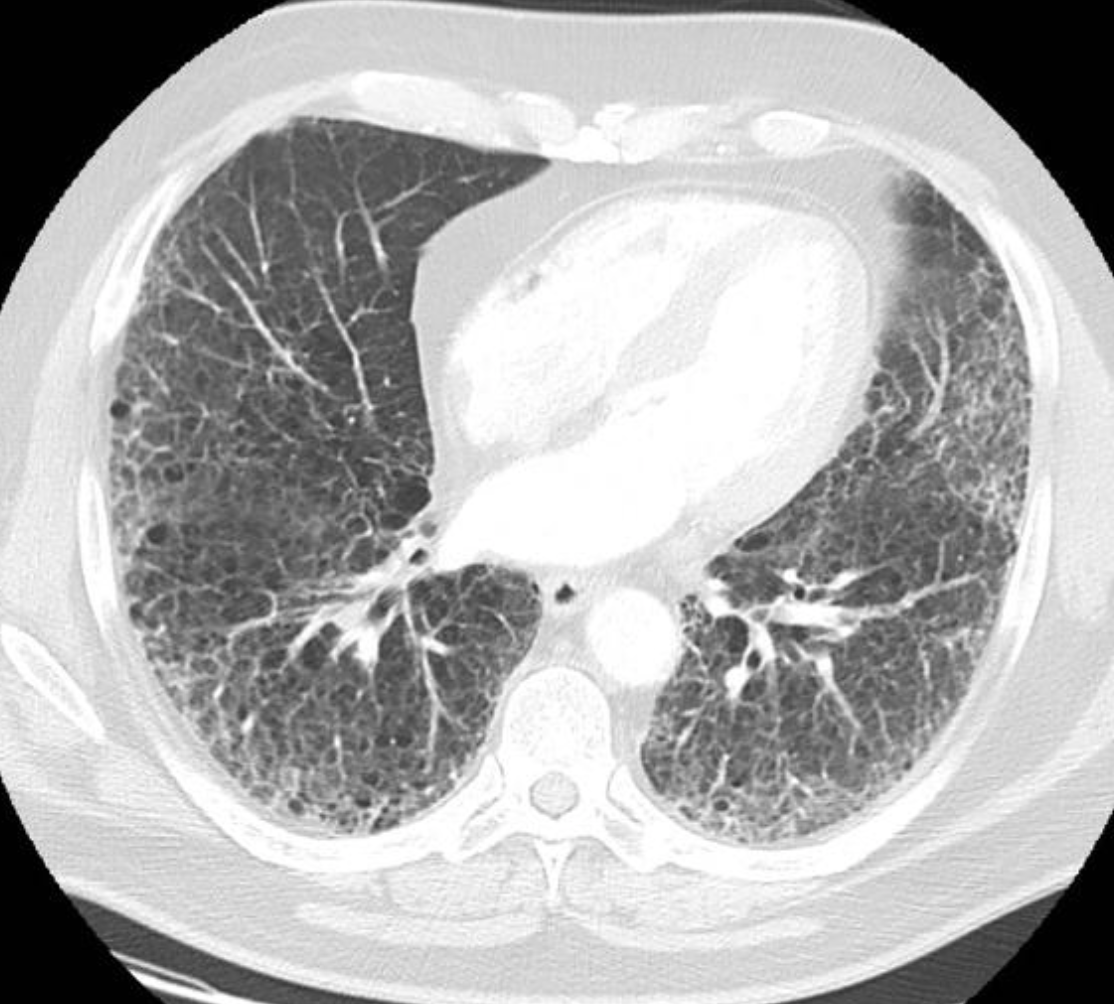

ACUTE INTERSTITAL PNEUMONIA

• Appears similar to ARDS but often with a symmetric Lower Lobe distribution

• EXUDATIVE PHASE (shown in pic one case)

• GGO

• Consolidation

• ORGANISING PHASE (pic two)

• architectural distortion

• traction bronchiectasis

• Honey combing